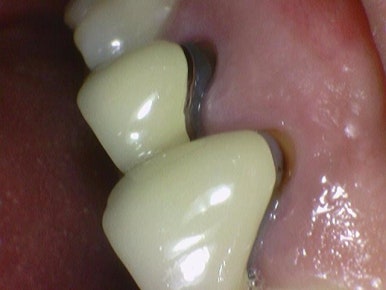

↓예전의 PFM크라운은 도자기 부분 깨진다거나

PFM은 도자기 아래 금속부분이 노출되는 등의 문제가 있었습니다.

PFM 크라운 2개를 심미 목적등으로 지르코니아크라운으로 변경. 시청역치과

위의 사진처럼 오래된 PFM크라운을 지르코니아 크라운으로 변경하기도 합니다.